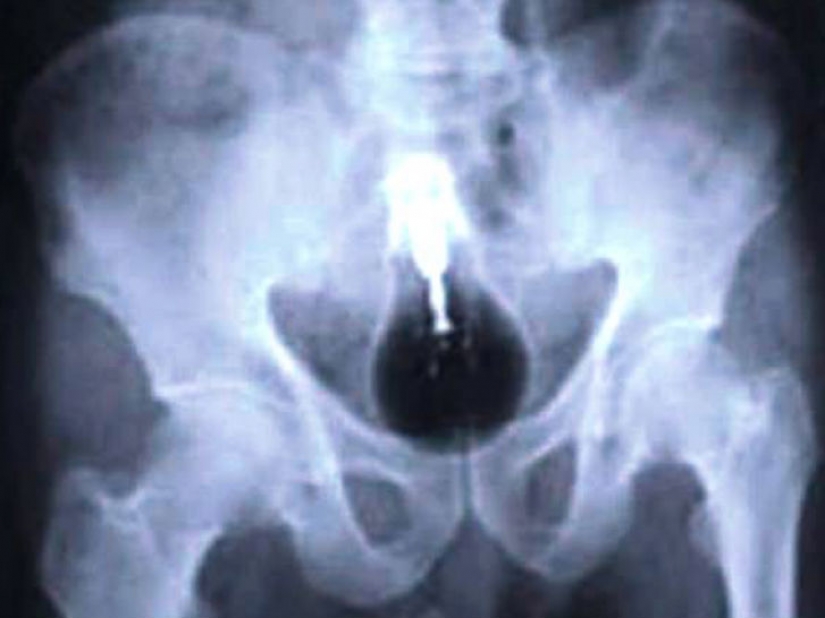

And the prisoners swallowed a cell phone.